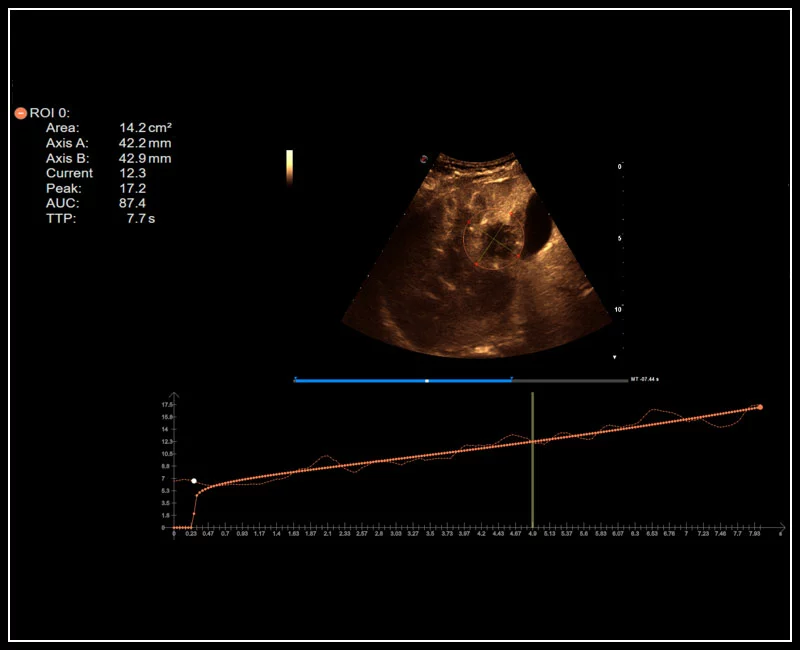

MyLab™9 Platform - QPack CnTI™ perfusion analysis post RF ablation

MyLab™9 Platform - QPack CnTI™ perfusion analysis post RF ablation

MyLab™E80 - CEUS - Liver

MyLab™E80 - CEUS - Liver

MyLab™X8 Platform - Contrast session with CnTI™ and Q-Pack

MyLab™X8 Platform - Contrast session with CnTI™ and Q-Pack

MyLab™A50 - Liver CnTi

MyLab™A50 - Liver CnTi